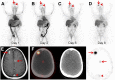

FIGURE 3.

46-y-old woman with both HER2-positive and HER2-negative primary breast malignancies and recently diagnosed brain metastases. Sequential maximum-intensity-projection images 1 d (A), 2 d (B), 6 d (C), and 8 d (D) after administration of 89Zr-pertuzumab. Blood-pool and liver background cleared on sequential images. Activity excreted by bowel was seen on days 1 and 2. Bilateral kidney activity was visualized on all days. Increasing activity in foci overlying skull was seen as time progressed (arrows). Decreasing activity was seen in blood pool of superior sagittal sinus (arrowheads). (E) Gadolinium-enhanced T1-weighed MR image of brain demonstrated enhancing brain metastases (arrows) and superior sagittal sinus (arrowhead). (F) Axial fused PET/CT, CT, and PET images 8 d after 89Zr-pertuzumab administration demonstrated avidity in brain metastases (arrows) and minimal residual avidity in superior sagittal sinus (arrowhead).